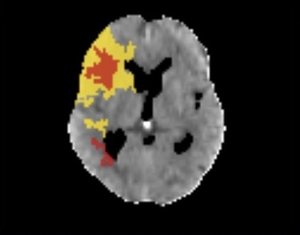

Com a interpretação do software, tudo ficou mais nítido. A cor vermelha representa a porção do órgão que já "morreu" devido à obstrução provocada pelo coágulo, e o amarelo, as zonas em sofrimento, que podem ser salvas se a circulação for restabelecida logo. Agora, mesmo profissionais com pouca experiência estão habilitados a operar o e-STROKE.

O sistema é capaz de colorir as regiões do cérebro que foram comprometidas em decorrência do entupimento do vaso sanguíneo. Antes, eram observadas apenas gradações de cinza. O ponto exato onde ocorreu o AVC também é mostrado.

Em vermelho, aparecem as regiões já "mortas" pela falta de circulação sanguínea, o que resultará em sequelas. Em amarelo, visualizam-se aquelas que ainda estão em sofrimento e podem ser salvas. À medida em que o tempo vai passando, as zonas em amarelo vão morrendo também. O novo programa de computador dá mais agilidade aos médicos, que podem iniciar o tratamento antes e com mais precisão, evitando incapacitações permanentes e até a morte do paciente. A depender do caso, se as condutas são iniciadas com rapidez, o doente pode se recuperar plenamente.